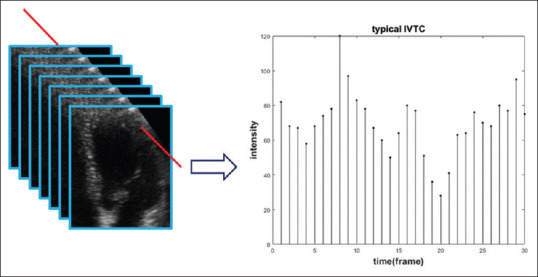

Methods: In this work, we have proposedto increase the frame rate temporally for a sequence of three-dimensional (3D) echocardiographyframes to make tracking more accurate. To increase the number of frames, cubic B-spline is usedto interpolate between intensity variation time curves extracted from every single voxel in theimage during the cardiac cycle. We have shown that the frame rate increase will result in trackingaccuracy improvement.